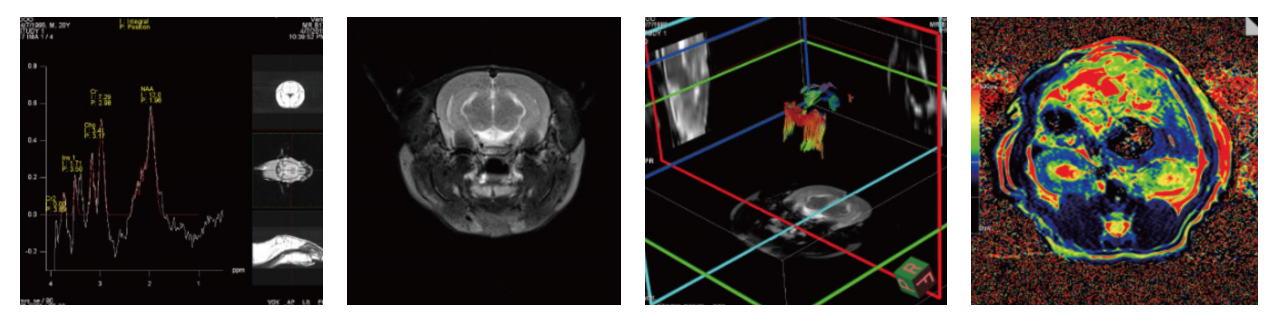

图2 结果展示

案例展示

脑部核磁检测应用

图3 脑分数各向异性(FA)参数。(A)在海马上使用放大 (B)海马层三个分层:辐射层、分子层和分子层

参考文献: 图3 doi: 10.1038/s41598-022-15511-0

(2)结肠癌核磁检测应拥

图4 MN-EPPT增强的MRI。a实验动物和对照动物的对比前和对比后图像显示肿瘤中MN-EPPT的积累(箭头)。b与未接受化疗的对照组1相比,实验组动物肿瘤的deltaT2值显著降低(*P < 0.05)。c对deltaT2值变化的定量分析显示,实验组SD和PD动物肿瘤之间的T2弛豫时间有显著性差异(*P < 0.05)。d对照组3和4组之间的deltaT2值差异无统计学意义。

参考文献:图 4 doi:10.1007/s11307-019-01326-5.